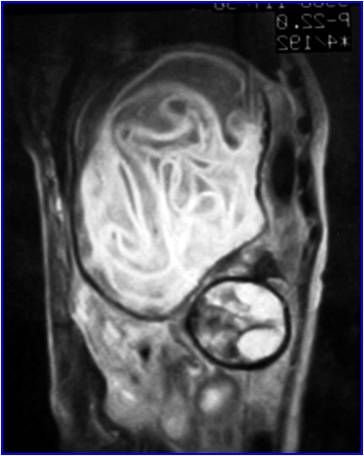

Can you diagnose this mostly asymptomatic patient but with weight loss and abdominal discomfort?

Case submitted by Saeed Rad, M.D., radiologist, to radRounds Radiology Network.